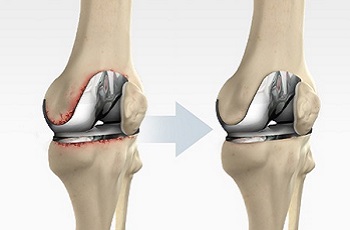

Knee replacement surgery is referred to as the surgical procedure that allows for replacing an arthritic or damaged knee with a metal, plastic, or ceramic device known as a prosthesis. This enables the patient to carry out movement similar to that of the healthy and natural knee. Although, the surgery can be performed to improve the conditions of the respective joint such as the ankle, wrist, shoulder, and elbow, knee and hip surgery are commonly performed joint replacement procedures. As the best orthopedic and joint replacement surgeon, Dr. B.R.Bagaria uses state-of-the-art techniques to help patients manage the various orthopedic disorders and knee-related problems. Moreover, patients with musculoskeletal and joint dysfunction or injuries are also provided quality treatment.

Knee replacement surgery is primarily recommended to patients who are aged 55 years or more and suffering from chronic pain conditions resulting in limited mobility of the patient. Knee replacement surgery or arthroplasty is one of the widely performed surgeries to overcome the pain caused by knee joints damaged due to arthritis, any trauma injury, etc. The outcome of the surgery can be observed in terms of enhanced mobility of the joint. The surgery may cost around Rs. 1,50,000. But it might change depending on a number of factors such as the cost of the knee implant, the hospital charges, and the fee charged by the joint replacement surgeon, the expertise of the surgeon, and the technique used for the surgery.